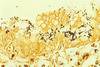

This leukocyte is unique to the guinea pig. What is it called?

Kurloff Cell

- Origin is controversial

- Highest concentration in pregnant females

- Thought to play a role in creating a physiological barrier between fetus/mother